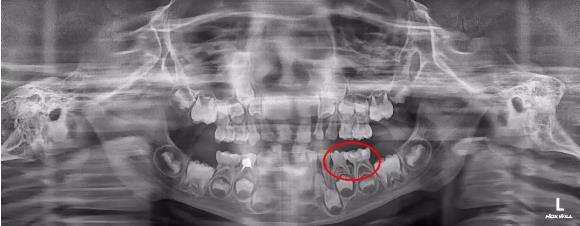

孩子喊牙疼,家長可別掉以輕心。最近,一個5歲的小朋友患了蟲牙,爸爸媽媽帶他到就近的診所治療,但是由于小朋友不配合,根管治療未能徹底進行,原本需要封的藥沒能封進去。所以一周之后,孩子再次喊牙疼,隨之而來的是面部腫脹。眼瞅著孩子的臉越腫越大像含了個饅頭,嘴巴也張不開,飯也吃不下,焦急萬分的家長前往第一口腔光谷院區(qū)求醫(yī)。

經(jīng)黃薇院長檢查,小朋友有頰側(cè)瘺管、根尖膿腫、間隙感染等癥狀,已經(jīng)形成蜂窩組織炎。蜂窩組織炎是一種由金黃色葡萄球菌、溶血性鏈球菌或腐生性細菌引起的皮膚和皮下組織廣泛性、彌漫性、化膿性炎癥,嚴重的患者可能出現(xiàn)敗血癥等危及生命的癥狀。

為了緩解小朋友的緊張情緒,本次治療是在吸入麻醉下進行,在舒適無痛的情況下,黃薇院長對兩顆患牙分別進行了根管治療和金屬預(yù)成冠修復(fù)操作,以及膿腫切排、搔刮、拔髓封藥等操作。其中膿腫切排操作起來比較復(fù)雜,首先黃薇院長小心將小朋友的膿腫部位切開,然后根據(jù)膿腔的位置和大小放置合適的引流條,這位小朋友足足排出100ml膿液,最后經(jīng)過生理鹽水沖洗、上藥,牙齒腫痛的問題才得到緩解。